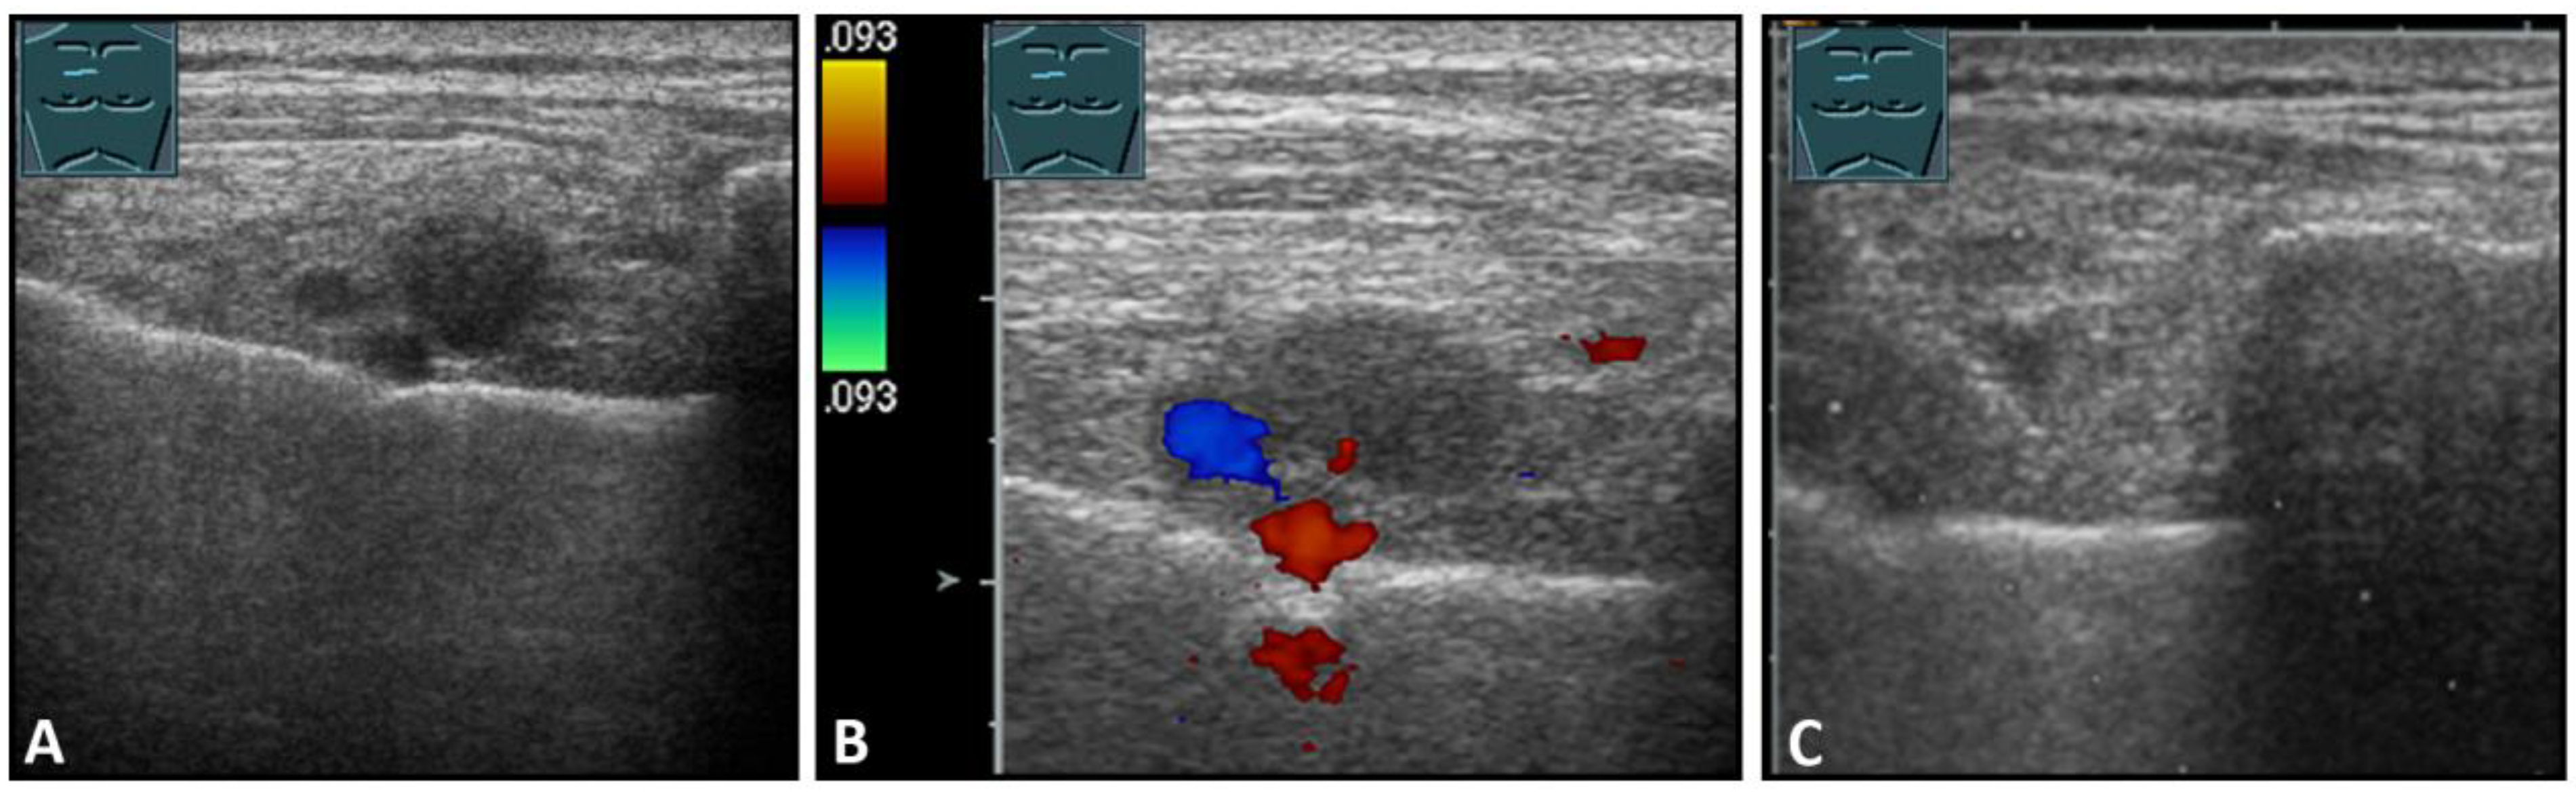

Figure 10.

Visualization of lymph node metastases parasternal to breast carcinoma in B-mode US (A) and CDS (B), with histologic confirmation (C).